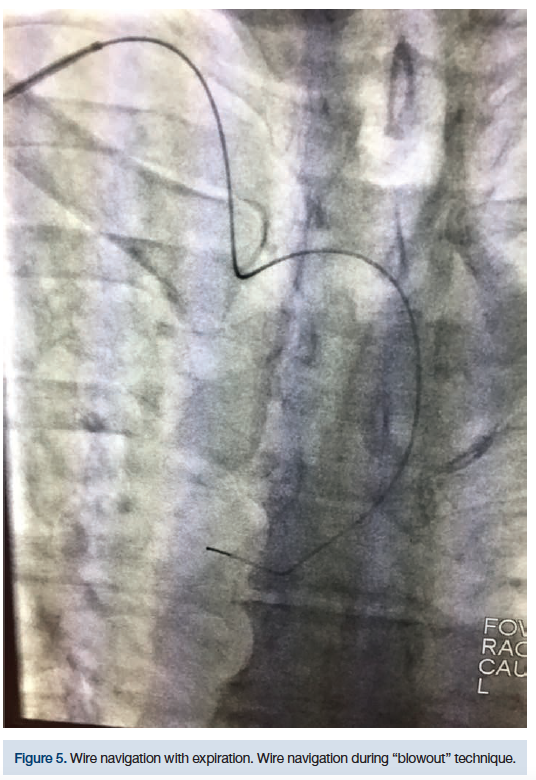

This technique was initially used on a 68-year-old female, diabetic, 5 feet, 4 inches tall, hypertensive, with severe RST (Figures 5-8). Despite several different catheter positions, wires, and extensive deep inspirations, the wire was repeatedly biased towards the descending aorta. Prior to bailing out to an alternative approach, we hypothesized that doing the exact opposite might gain us access to the AA. After several minutes of fluoroscopy and extensive deep inspirations disallowed navigation, a single deep expiration allowed our wire and catheter access into the AA with minimal fluoroscopy.

Upon catheters being placed at the origin of the brachiocephalic trunk or the transverse aorta, the patient is asked to take a deep breath in and “blow” it all out. At that moment, the operator will advance the guidewire in an effort to access the AA. Logic dictates that if a deep inspiration straightens RST for catheter navigation, then a deep expiration would amplify tortuosity, disallowing catheter navigation. While inspiration distends out RST, it also creates a rigid pathway for catheters (Figure 9).

While distended, it is possible this pathway may bias catheters towards the descending aorta. However, a deep expiration “softens” the anatomy, to a small degree, increases the lumen size, and may improve the entry angle into the AA. This may allow a wire to pass into the AA with relative ease. This technique has worked several times on patients that have had severe RST. The “blowout” technique can be attempted when conventional methods of accessing the AA fail and/or when deep inspiration continuously biases catheters towards the descending aorta.